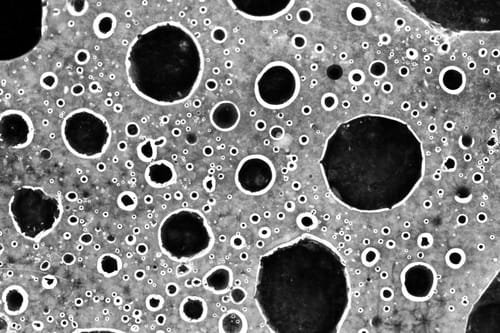

“It’s a molecule with a radioactive particle attached which finds the cancer cell,” Radboudumc nuclear medicine expert James Nagarajah told the AD.